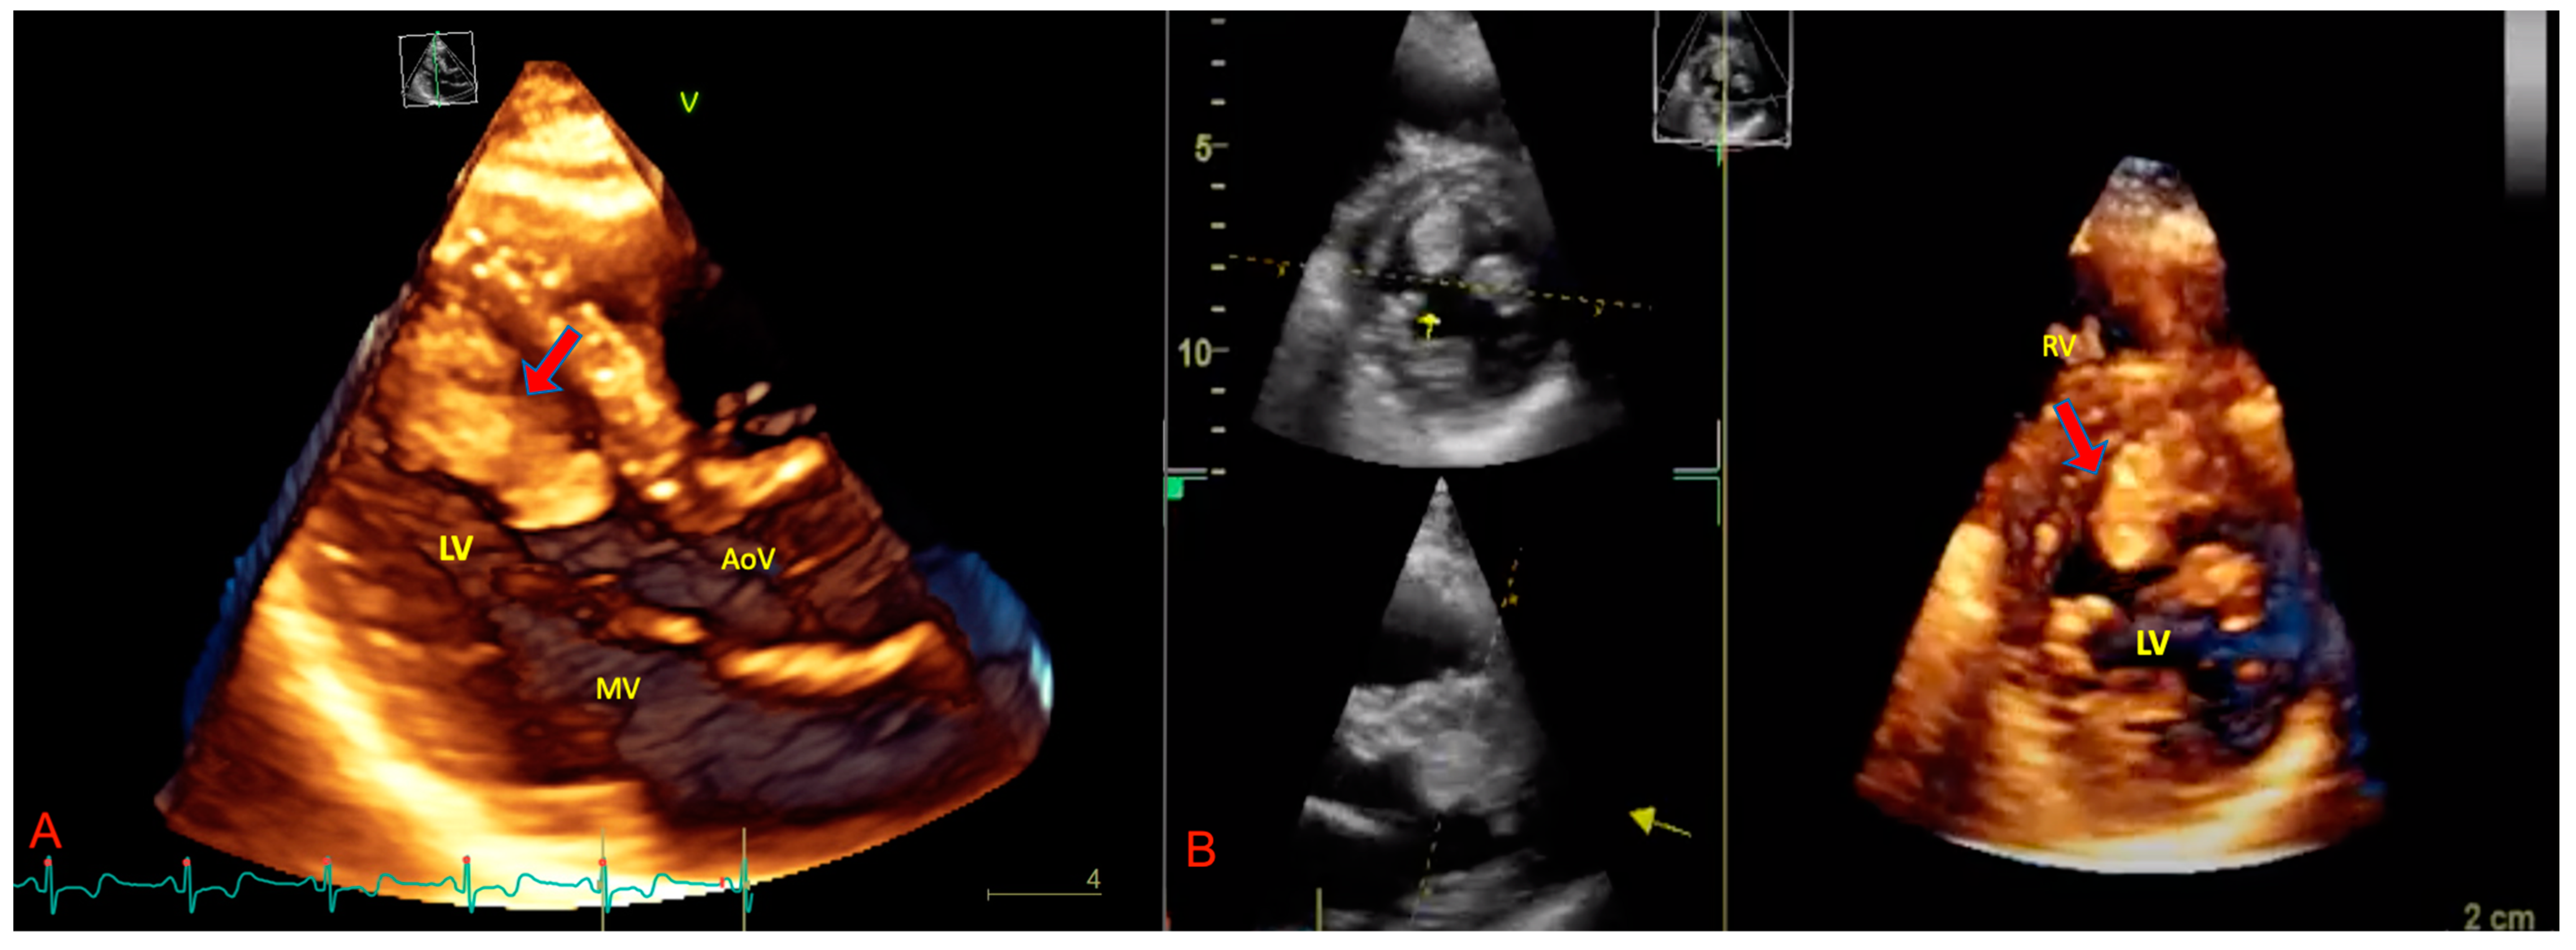

3. The Role of Echocardiography in pSTS-h

- Guta, A.C.; Badano, L.P.; Ochoa-Jimenez, R.C.; Genovese, D.; Previtero, M.; Civera, S.; Ruocco, A.; Bettella, N.; Parati, G.; Muraru, D. Three-dimensional echocardiography to assess left ventricular geometry and function. Expert Rev. Cardiovasc. Ther. 2019, 17, 801–815. [Google Scholar] [CrossRef] [PubMed]

- Asch, F.M.; Bieganski, S.P.; Panza, J.A.; Weissman, N.J. Real-Time 3-Dimensional Echocardiography Evaluation of Intracardiac Masses. Echocardiography 2006, 23, 218–224. [Google Scholar] [CrossRef]

- Gok, G.; Elsayed, M.; Thind, M.; Uygur, B.; Abtahi, F.; Chahwala, J.R.; Yıldırımtürk, Ö.; Kayacıoğlu, İ.; Pehlivanoğlu, S.; Nanda, N.C. Incremental value of live/real time three-dimensional transesophageal echocardiography over the two-dimensional technique in the assessment of primary cardiac malignant fibrous histiocytoma. Echocardiography 2015, 32, 1164–1170. [Google Scholar] [CrossRef]

- Reddy, V.K.; Faulkner, M.; Bandarupalli, N.; Nanda, N.C.; Singh, P.; Dutta, R.; Singh, A.; Pothineni, K.R.; Dod, H.S.; Bhardwaj, R.; et al. Incremental Value of Live/Real Time Three-Dimensional Transthoracic Echocardiography in the Assessment of Right Ventricular Masses. Echocardiography 2009, 26, 598–609. [Google Scholar] [CrossRef]